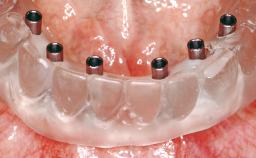

Conventional Loading of Eight Implants in the Maxilla and Final Restoration with a Full-Arch Gold-Ceramic FDP

# of Implants 8

Defining Characteristics Fully edentulous upper jaw to be rehabilitated with four or more implants

Modality Fixed hybrid bridge on 5+ implants